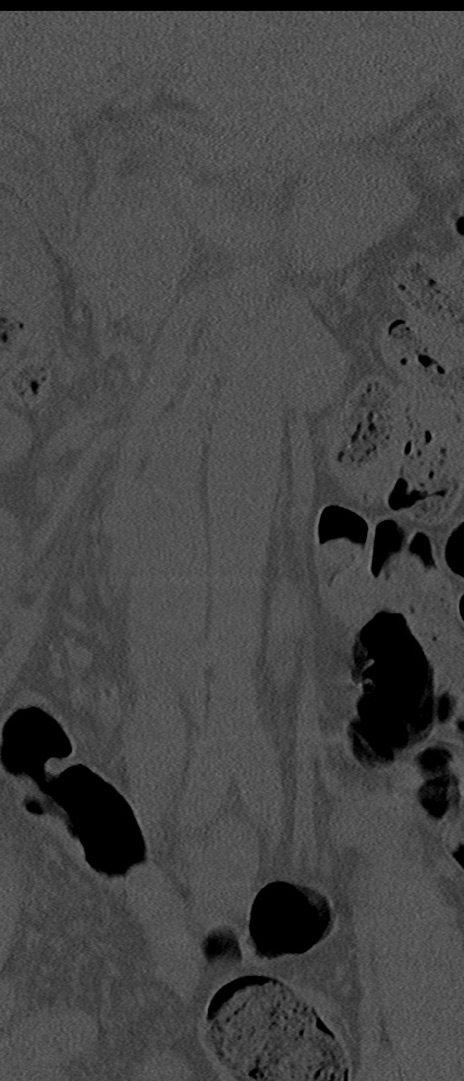

【整形】TIPS症例4 腰椎CT(冠状断像)

腰椎CT